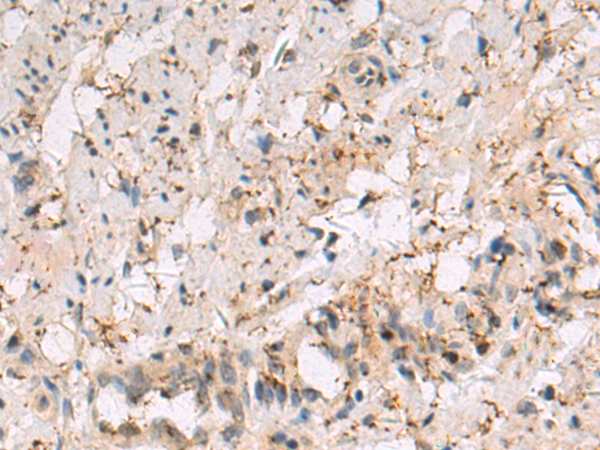

Applications: |

IHC |

IHC positive control: |

Human breast carcinoma tissue |

IHC Recommend dilution: |

50-100 |